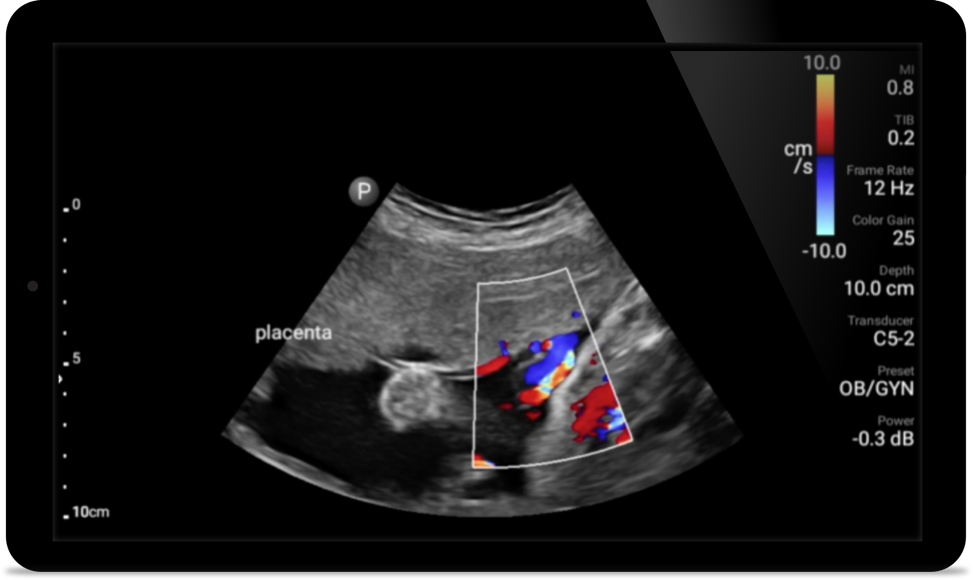

• 5 to 2 MHz extended operating frequency range • 50mm radius of curvature • 2D, color Doppler, M-mode, advanced XRES and multivariate harmonic imaging, SonoCT • High-resolution imaging for deeper applications: abdominal, gall bladder, OB/GYN and lung imaging preset optimizations